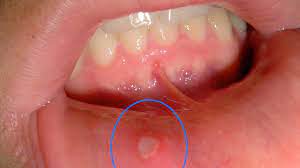

See full list on wikihow.com Heal mouth sores & stop future outbreaks. Some sores inside the mouth are usually raised and filled with fluid just like blisters. How do you cure a gum blister? Apply ice to the sore. Breakthrough red light device that treats cold sores in 2 days. Avoid hot foods and beverages, spicy and salty foods, and anything that contains citrus. What causes blisters in the mouth and lips?

See full list on wikihow.com Some sores inside the mouth are usually raised and filled with fluid just like blisters. See full list on wikihow.com Treat fever blisters on the outside of the lips and mouth now. How do you cure a gum blister? Avoid hot foods and beverages, spicy and salty foods, and anything that contains citrus. Heal mouth sores & stop future outbreaks. What causes blisters in the mouth and lips? Jun 13, 2019 · simply mix a teaspoon of sea salt in half a glass of lukewarm water and make a solution. Heal mouth sores & stop future outbreaks. Apply ice to the sore. Breakthrough red light device that treats cold sores in 2 days. How do you treat blisters on gums?